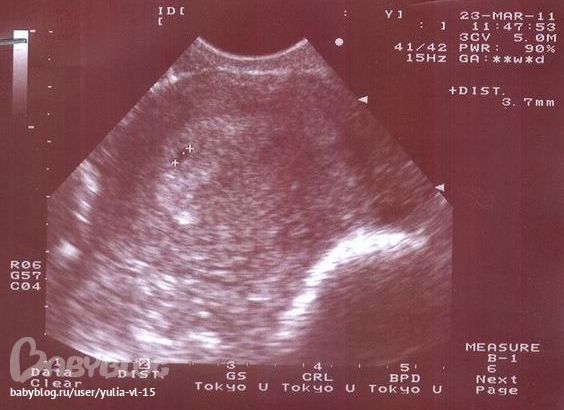

Вот так мы узнали про нашего чудика))

Вот первая "фотография" Сашеньки:

Здесь малышику всего три недельки)